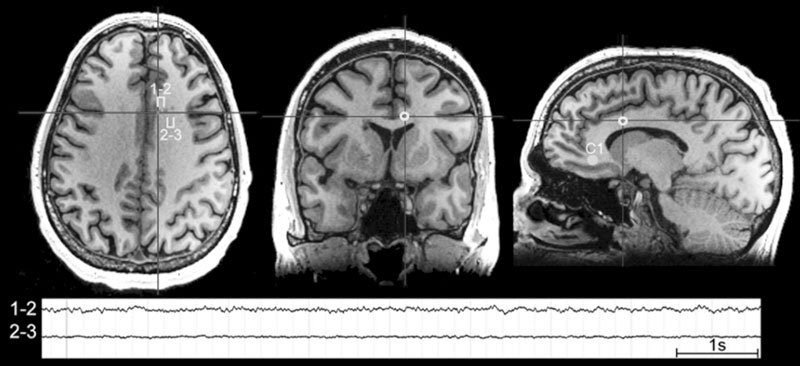

Чтобы разобраться в функциях сна, Пигарев выбрал очень простую стратегию. Он лишал животных сна, а дальше наблюдал за ними. Первый неутешительный вывод последовал практически сразу. Животное, лишенное сна, через некоторое время обязательно умирало, но перед этим у него наблюдалось нарушение работы желудочно-кишечного тракта, потом начинала вылезать шерсть, а на теле появлялись язвы. Когда тела животных были вскрыты, обнаружилось, что все внутренние органы повреждены. Все, кроме одного – мозга. Тогда стало понятно, что наш мозг никогда не спит. Если раньше нам казалось, что ночью он отдыхает, чтобы сбросить психическое напряжение, то в свете экспериментов по депривации сна, стало очевидно, что мозг не отдыхает никогда. Когда мы спим, он работает даже более напряженно. На иллюстрации ниже это хорошо видно.

Суммарная электрическая активность коры мозга кошки при переходе от бодрствования ко сну

Во время бодрствования мозг использует все свои вычислительные ресурсы для обработки сенсорных данных, поступающих из внешнего мира, а в режиме сна он переключается на информацию от внутренних органов, объемы которой, как оказалось, даже больше. Соответственно, недостаточный или плохой сон – это не просто отсутствие психического тонуса на следующий день, это еще и не оказанная вовремя помощь пищеварительной, сердечно-сосудистой, иммунной, репродуктивной и всем остальным системам нашего организма. И те из нас, кто пренебрегает сном или не обеспечивает для него необходимые условия, на самом деле просто не дают мозгу заниматься техобслуживанием тела. Последствия касаются не только психики, памяти и интеллекта, недостаток сна приводит к болезням, гормональным сбоям, дисфункциям внутренних органов, снижению иммунитета и т. д.